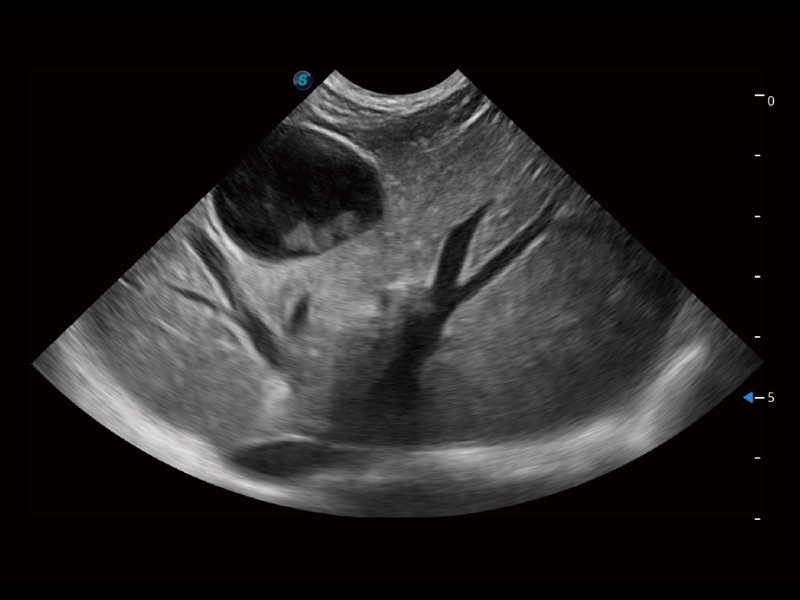

貓、中小型犬及小型異寵動(dòng)物

ProPet 70 進(jìn)一步提升了微米成像算法,更加注重對(duì)基礎(chǔ)原始圖像的還原和保留,在有效減少斑點(diǎn)噪聲、增強(qiáng)組織邊界顯示的同時(shí),避免過(guò)度優(yōu)化丟失真實(shí)的解剖信息。

ProPet 70專為動(dòng)物醫(yī)生設(shè)計(jì),對(duì)不同的動(dòng)物體型和生理結(jié)構(gòu)作出了針對(duì)性的優(yōu)化。通過(guò)動(dòng)物影像專用軟件,可滿足個(gè)性化的應(yīng)用需求,幫助動(dòng)物醫(yī)生獲得更精確的診斷數(shù)據(jù)。

為精細(xì)結(jié)構(gòu)及組織邊緣提供高清晰度的圖像和更大的成像視野。幫助減輕醫(yī)生的用眼疲勞,快速精準(zhǔn)獲得測(cè)量的數(shù)據(jù)。